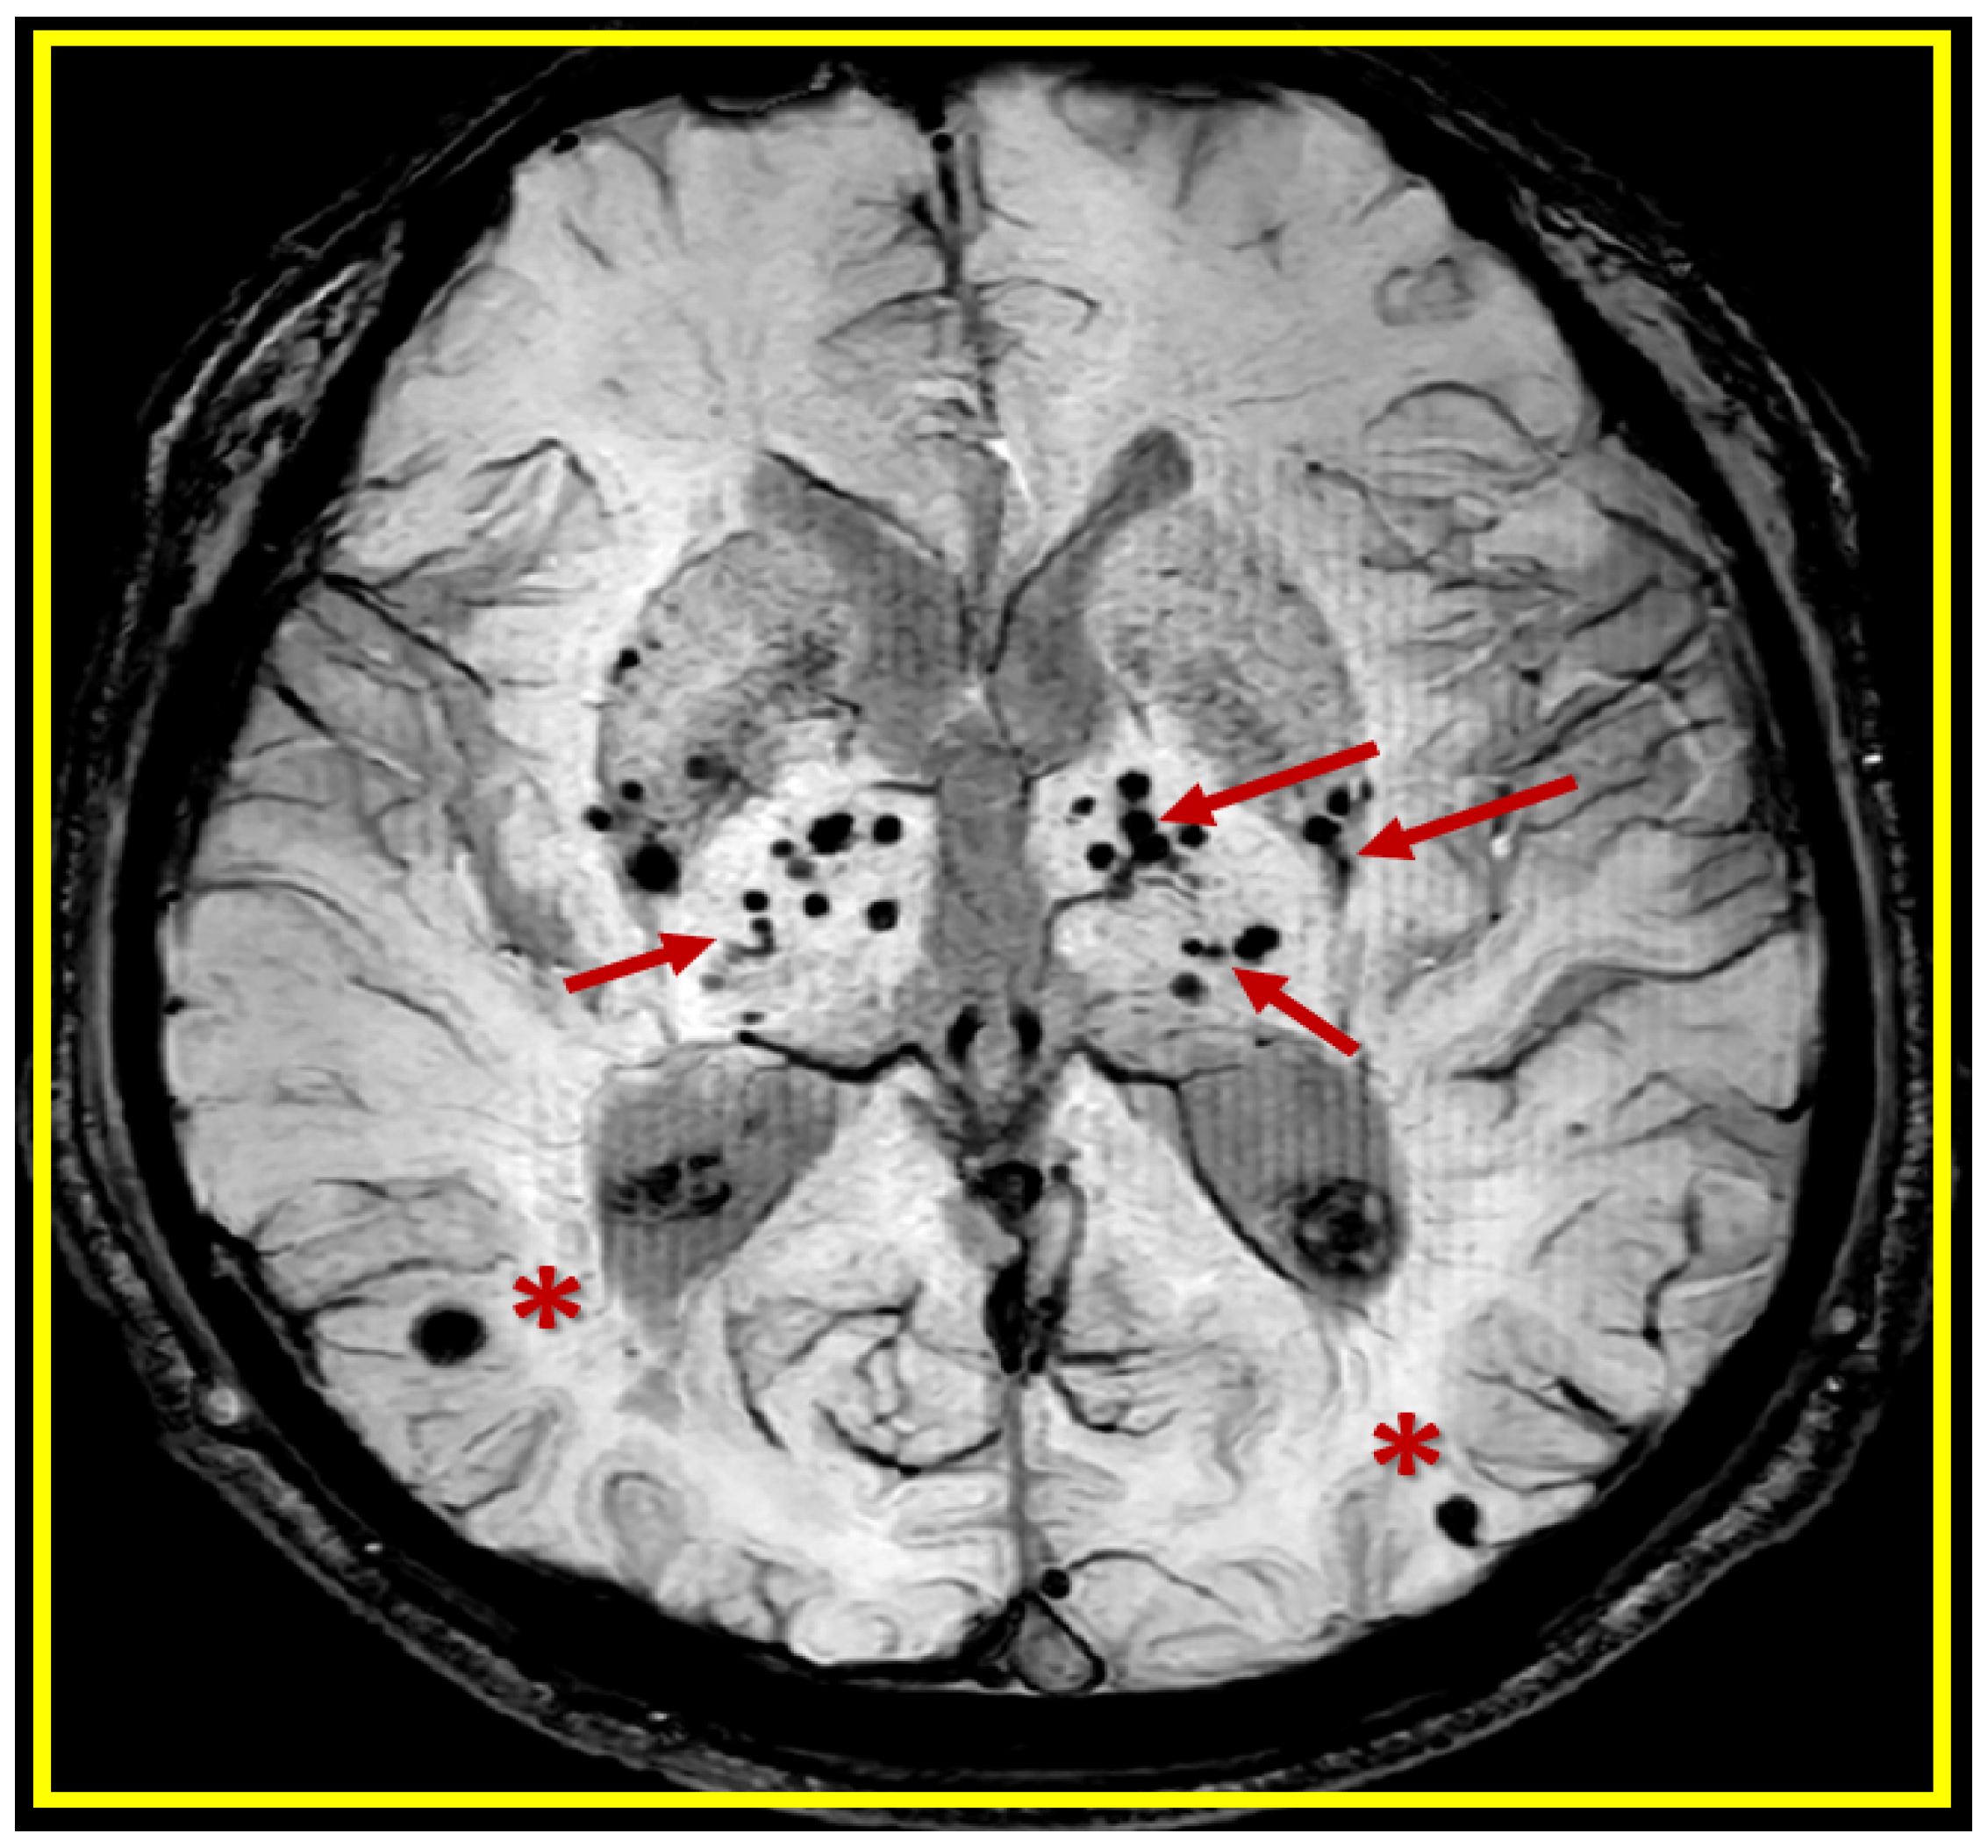

:1. Introduction

2. A Possible Sequence of Events in the Development of Cerebral Microvessel Bleeds (CMBs)

3. Transmission Electron Microscopy (TEM) Imaging of BECact/dys), BBBdd with CMBs